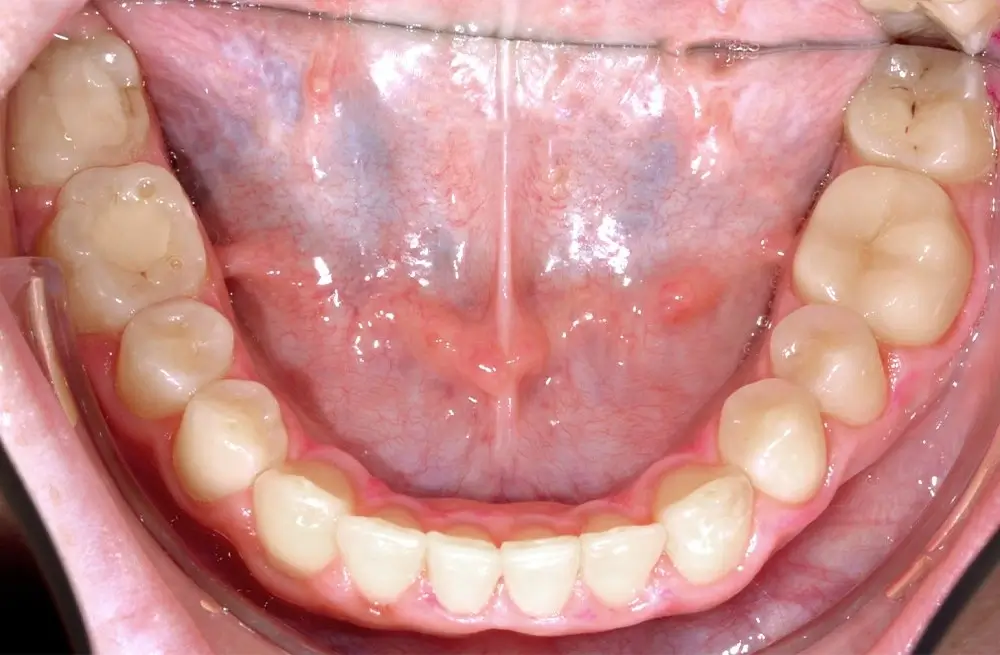

Открытый прикус - Кейс 2

Эффективность устранения дефекта прикуса посредством элайнеров FlexiLigner.

22

Количество кап НЧ

Результаты лечения